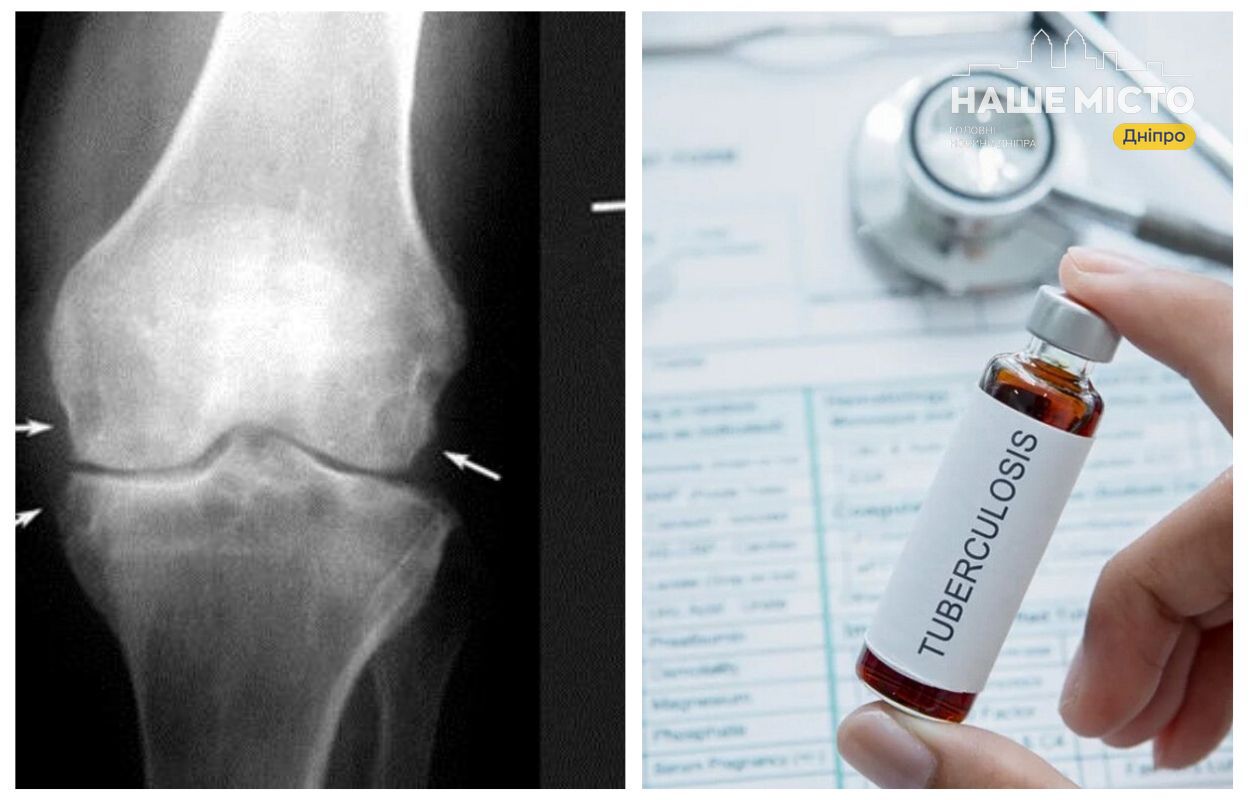

- Лікування деяких форм туберкульозу, як-от кісток і центральної нервової системи, потребує тривалого курсу — від 9 до 10 місяців.